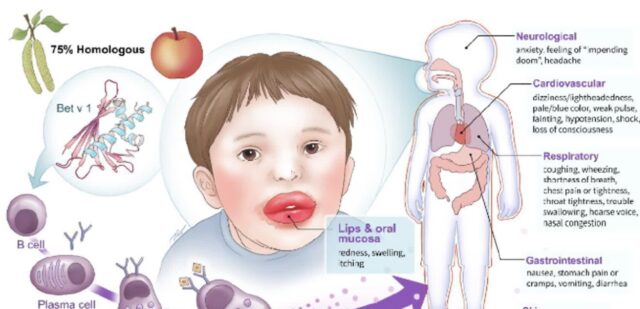

구강 알레르기 증후군 꽃가루 음식 알러지 관련있는 면역반응기전